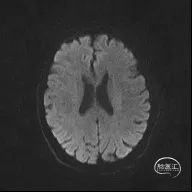

颅脑MR:脑内多发缺血灶、软化灶。